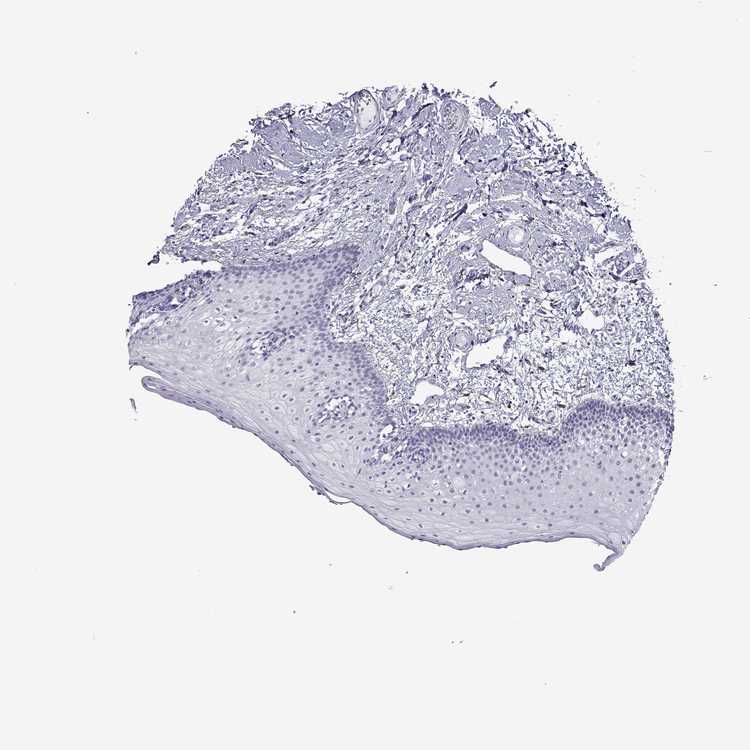

TISSUE PRIMARY DATA ORAL MUCOSA Show tissue menu

ORAL MUCOSA - Antibody stainingi

Antibody staining in the annotated cell types in the current human tissue is reported as not detected, low, medium, or high, based on conventional immunohistochemistry profiling in selected tissues. This score is based on the combination of the staining intensity and fraction of stained cells.

Each image is clickable and will lead to virtual microscopy that enables deeper exploration of all samples and also displays staining intensity scores, fraction scores and subcellular localization as well as patient and tissue information for each sample.

Antibody HPA066468

Squamous epithelial cells Not detected